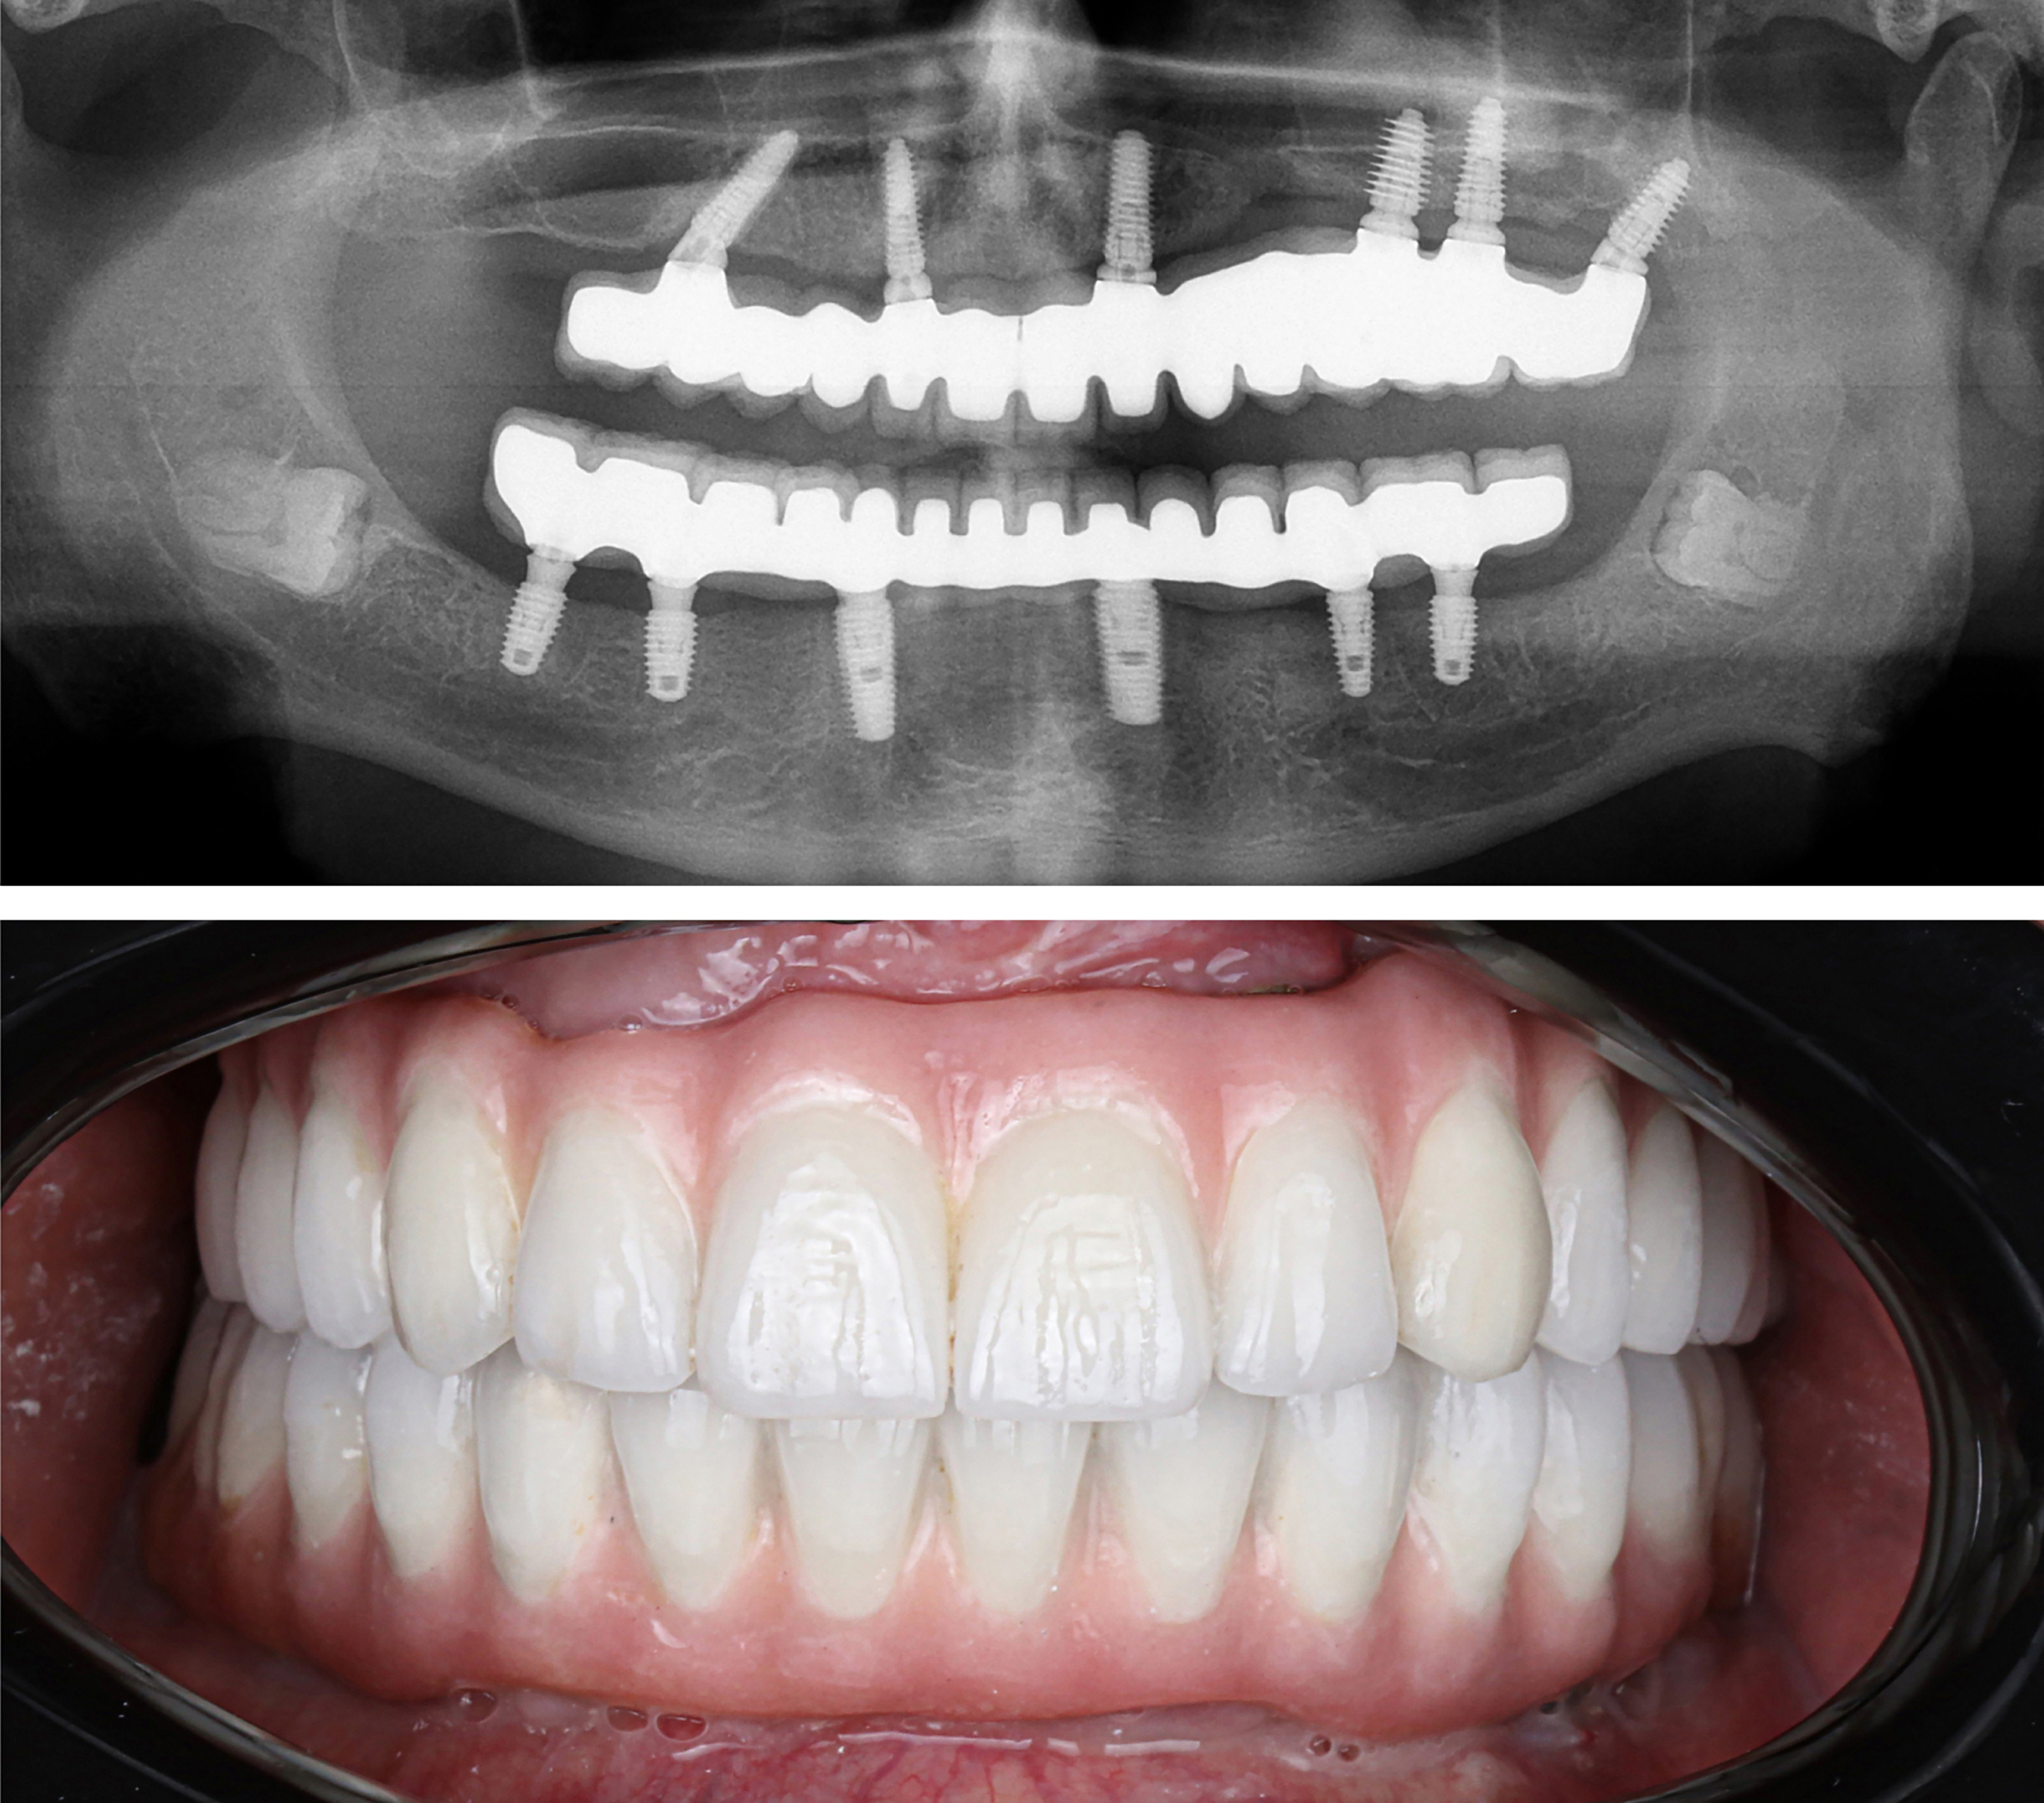

Example transformations achievable with dental implants

These images are for illustrative purposes only and do not represent actual patients treated at Karimi Dental.